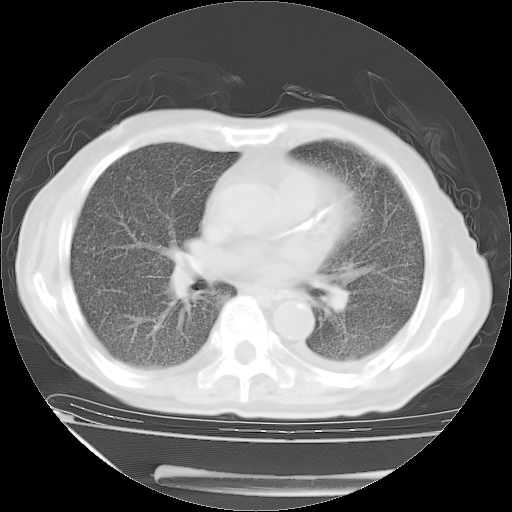

甲强龙80mg/日+抗结核治疗(异烟肼+利福霉素+乙胺丁醇)10天。复查肺部CT。

治疗10天肺部CT

补充下:5月9日胸部CT:似乎已见双下肺胸腔积液了,鉴于目前有下肢水肿,肝功示:白蛋白低,应注意多浆膜腔积液(漏出液可能大?),需注意!